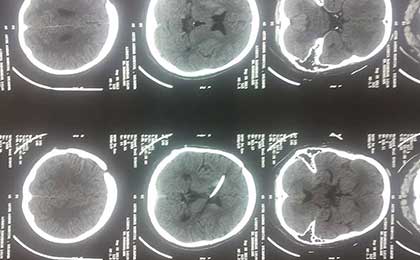

Complication of Shunt by Some Other Surgeon